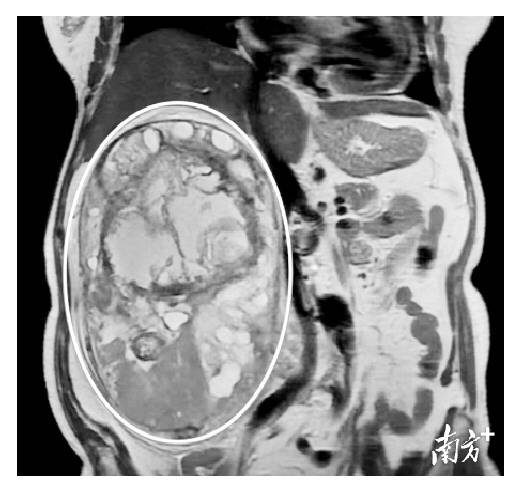

老人家这才下定决心到医院就诊,暨南大学附属第一医院肿瘤内科赵建夫主任接诊后,将她收住院做详细检查。检查结果显示,肿瘤囊实性,位于右侧腹膜后,长径22cm,与邻近腰大肌分界欠清,邻近脏器受压、移位,肝右叶6cm大囊肿。

在多学科的保驾护航下,李强医生手术团队成功为区奶奶实施腹膜后巨大肿瘤切除术+肝右叶大囊肿开窗术,术后病理示肿瘤性质为神经鞘瘤。